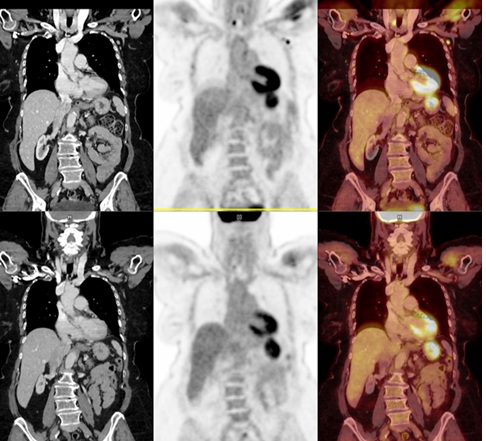

Immune responses among individuals are highly variable [12], and we chose to perform our analysis of axillary nodal uptake on patients with both post-COVID vaccine and post-Influenza vaccine FDG PET scans so each subject could serve as his/her own internal control. Overall, 20% of subjects show asymmetric and grade 3 (intense), defined as greater than liver background, axillary nodal uptake following recent COVID vaccination. In the small sub-cohort of patients with both recent FDG PET after COVID-19 vaccination as well as remote FDG PET after Influenza vaccination, 37% of post-COVID-19 vaccine PET scans shows intense axillary nodal uptake while none of the post-Influenza vaccine scans shows significant uptake (Figure 3). Although some correlative lymph nodes on CT measured slightly asymmetrically larger than contralateral nodes, none exceeded 1 cm in short axis diameter.

Figure 3: 70 year old female with diffuse large B cell lymphoma of the left lower extremity with COVID-19 vaccination in the left deltoid muscle 21 days prior to her FDG PET scan (top). SUVmax of the highest lymph nodes was 5.6 (short axis 9 mm correlative node on CT). An older FDG PET scan (bottom) was performed 19 days following intramuscular Influenza vaccination.  Laterality of Influenza injection is unknown but neither axilla showed any increased uptake.